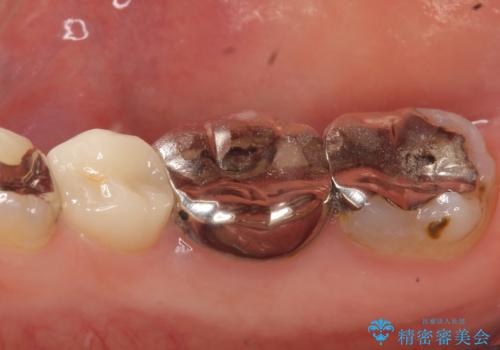

- 右下でものを咬むと歯茎が疼くので診て欲しいといらっしゃった方の症例です。

診査の結果右下6の歯の神経が死んでいたため、根管治療を行いました。